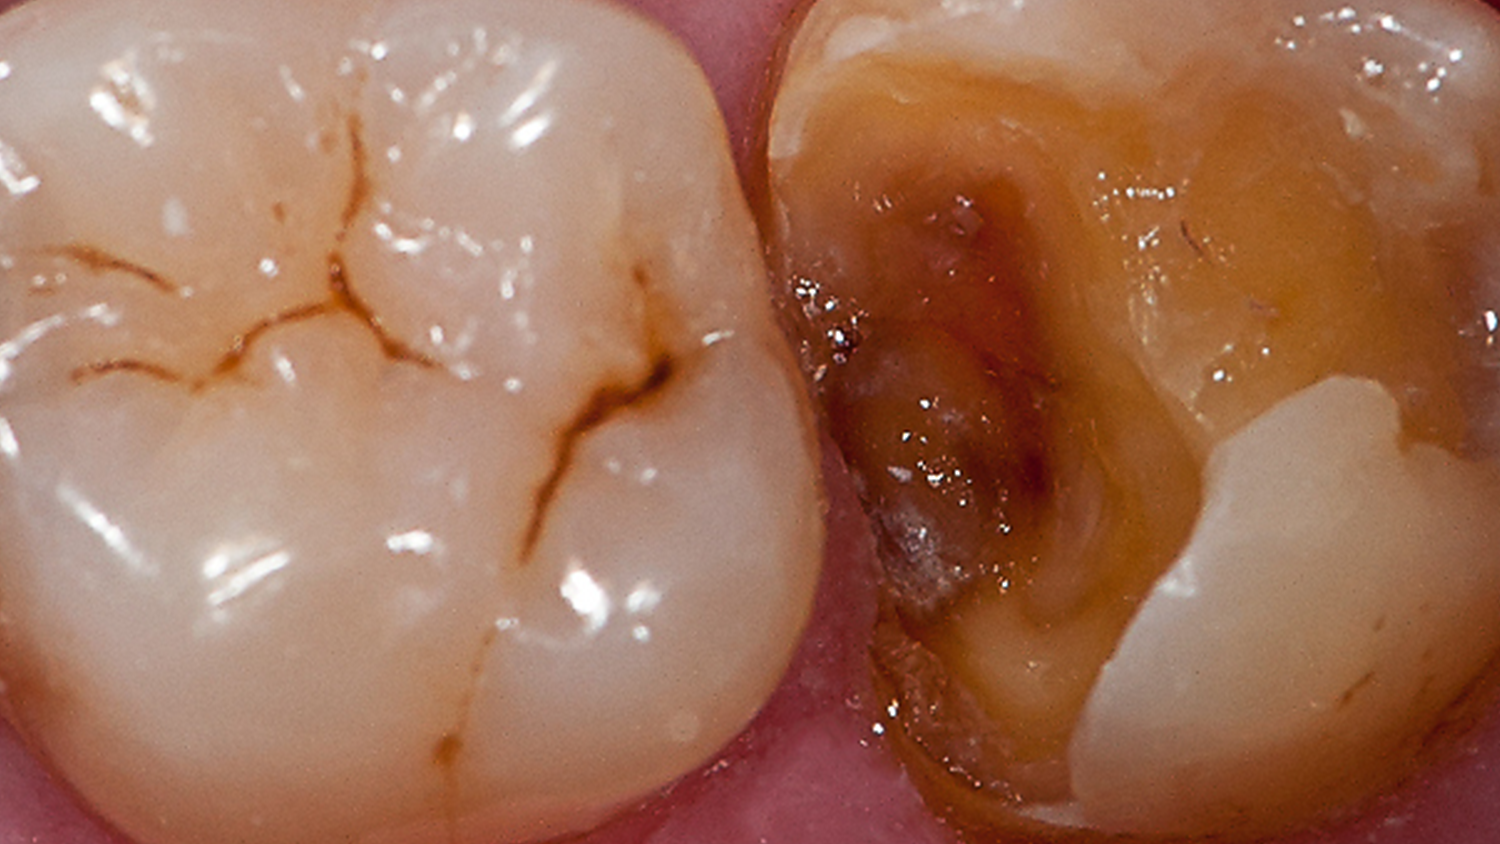

Case: Initial case showing defective and leaking old amalgam restorations.